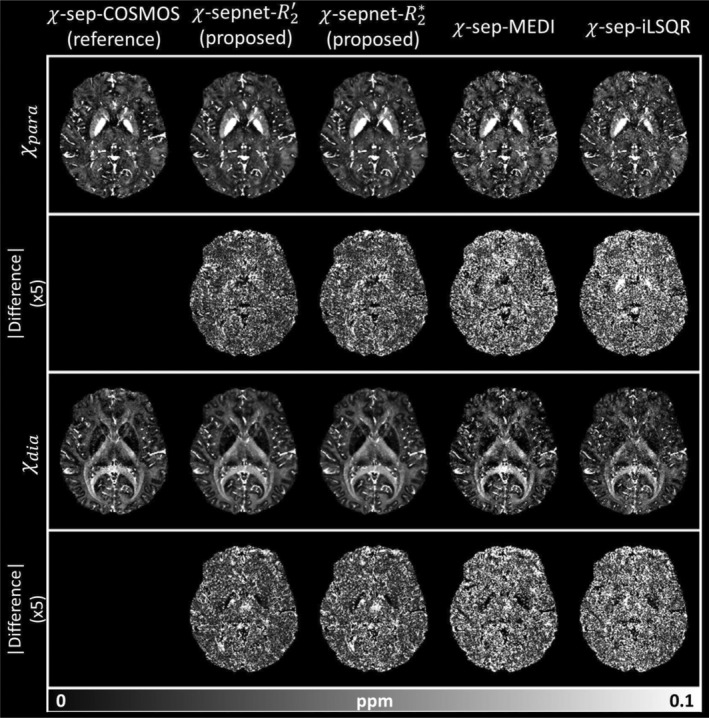

χ-sepnet: Deep neural network for magnetic susceptibility source separation

Human Brain Mapping, 2025